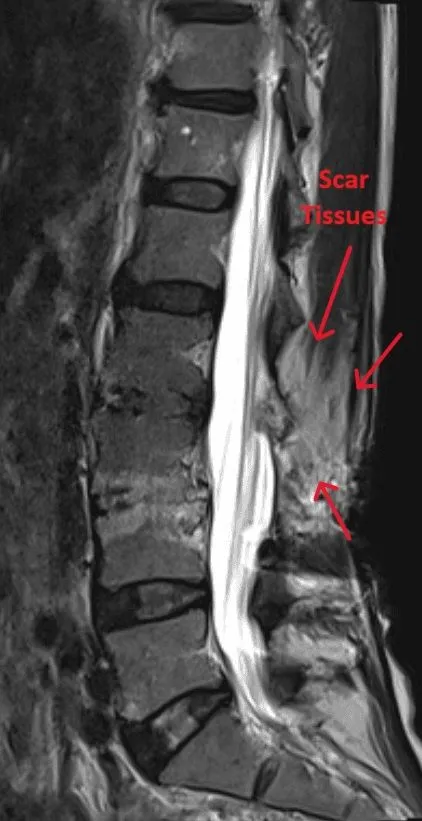

MRI scan showing scar tissue in the lumbar spine, labeled with arrows.

Excessive Scar Tissue

Extensive scar tissue formation around the spine and nerves causing persistent pain.